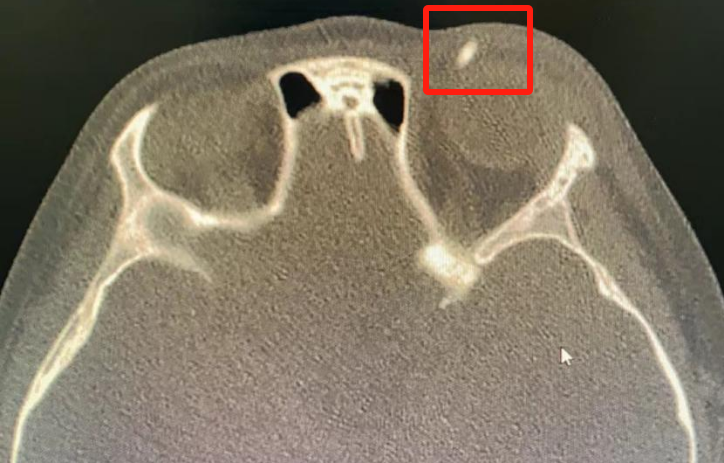

眼科醫(yī)生針對(duì)性地為孩子開(kāi)具了眼眶CT

排除是否眼眶內(nèi)留存了異物

眼眶CT結(jié)果提示

苗苗的眼瞼內(nèi)果然存有異物

眼科醫(yī)生判斷

這可能是一根斷掉的鉛筆芯!